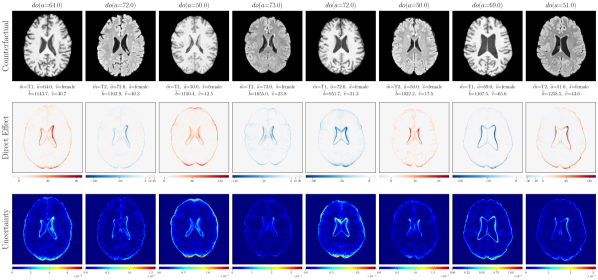

4.2 Brain Imaging Counterfactuals

To demonstrate our model’s ability to produce faithful high-fidelity counterfactuals of real data, we extend our approach to a real-world scenario involving brain MRI scans from the UK Biobank (Sudlow et al., 2015). As before, we start with an assumed causal generative process involving a set of observed variables as shown in Figure 4(a). The causal graph is medically informed and extends the scenario in Pawlowski et al. (2020) by: (i) introducing an additional MRI Sequence (T1/T2) binary variable to enable discrete counterfactuals; (ii) having directly. We used a scaled-up version of our exogenous prior HVAE as ’s mechanism and used (conditional) normalizing flows for the other mechanisms (see Appendix A.1). As shown in Figure 4, our deep SCM is capable of producing qualitatively sharp counterfactuals with localised changes according to the intervened upon parent(s) and the associated causal graph. Importantly, the identity of subjects is well preserved in all cases including null-interventions (i.e. nothing). Table 2 shows the counterfactual effectiveness results from random interventions on each variable. We observed satisfactory initial counterfactual effectiveness and significant improvements of post counterfactual training, demonstrating the merit of the proposed approach. Please refer to Appendix A.2 for notes on abduction uncertainty and D for additional results.

D.3 Extra Results

‘MRI Seq.’ counterfactuals

Post counterfactual training:

‘Sex’ counterfactuals

‘Age’ counterfactuals

‘Brain Volume’ counterfactuals

‘Ventricle Volume’ counterfactuals